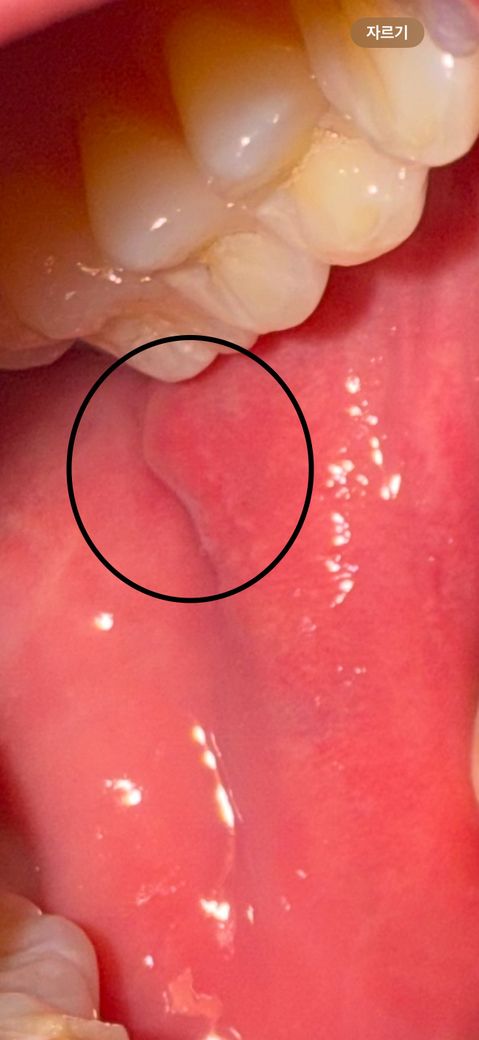

볼 점막에 난게 한달 넘게 안 사라집니다.

한달하고 1-2주 전에 볼 점막에 난 건데

처음보다 크기는 1/3 정도로 줄었으나

이 크기에서 2주째 그대로입니다.

가끔 커졌다가 다시 작아질 때도 있구요..

(한 번씩 혀로 만져보면서 확인합니다.)

통증은 처음부터 없던 것으로 기억하는데

단순 구내염이 아닌 다른 병일까요…?

• 1번 째 사진

• 안녕하세요. 배병제 의사입니다.

해당 병변에 대한 평가가 제한되지만, 위치가 침샘의 개구부라 추정되는데 해당 부위의 염증반응이 잘 사라지지 않고 있다면 이비인후과에서 원인을 찾아보시는 것이 좋겠습니다.